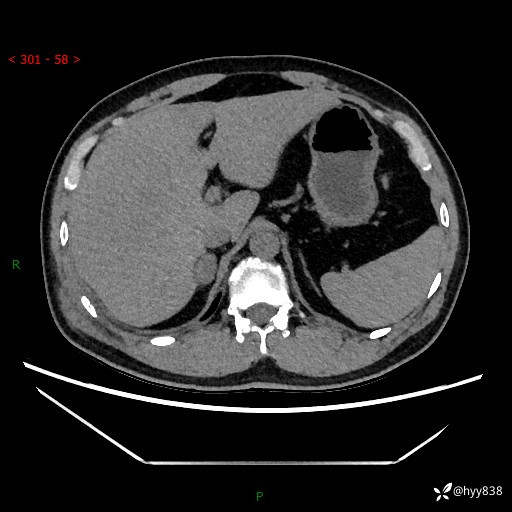

现病史:患者9月4日摔伤在深圳市宝安区中心医院行CT检查提示右侧肾上腺区结节(38*27mm),复查B超提示右侧肾上腺区可见一61*24mm异常低回声团,建议进一步检查。进一步完善增强CT后提示:右侧肾上腺区肿块及周围渗出改变,大致同前,考虑肾上腺腺瘤,不除外瘤内出血可能,否认阵发性头晕、头痛、出汗、乏力等不适,门诊以“ 右侧肾上腺肿瘤”收入住院。 起病来,患者精神、食欲、睡眠可,大便通畅,小便如上述,体力体重无明显改变。

肾上腺CT平扫

增强(动脉期+静脉期)